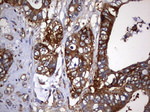

KRT7 Monoclonal Antibody (OTI3B7), TrueMAB™

Cytokeratin 7 blocks interferon-dependent interphase and stimulates DNA synthesis in cells. Involved in the translational regulation of the human papillomavirus type 16 E7 mRNA (HPV16 E7).

蛋白别名: CK-7; cytokeratin 7; Cytokeratin-7; K7; keratin 7, type II; keratin, 55K type II cytoskeletal; keratin, simple epithelial type I, K7; Keratin, type II cytoskeletal 7; Keratin-7; Sarcolectin; type II mesothelial keratin K7; Type-II keratin Kb7